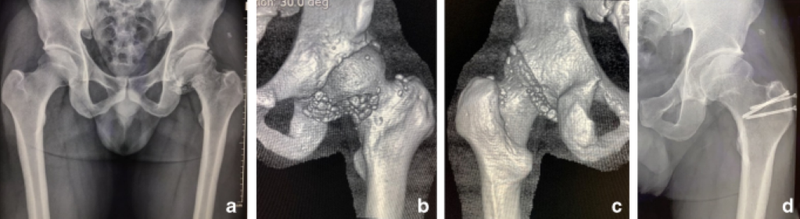

Chụp X quang khung chậu đơn giản rất hữu ích trong việc phát hiện các rối loạn tiềm ẩn ở khớp háng, nhưng nếu u sụn chưa bị vôi hóa thì khó có thể chẩn đoán phân biệt với viêm bao hoạt dịch. Do đó, thực hiện chụp CT hoặc MRI khi các triệu chứng không thể giải thích dễ dàng bằng các dấu hiệu X quang.

Chụp CT có thể cho thấy các khối u sụn bị vôi hóa hoặc không bị vôi hóa và mật độ của chúng thường thấp hơn so với mô cơ. Chụp X-quang các các u sụn bị vôi hóa cao có thể cho thấy kích thước tương đối đồng nhất, được bao quanh bởi các vòng mật độ cao không đều và các vùng mật độ thấp hơn bên trong.

Sự phát triển của u sụn khớp háng gây ra nhiều khó khăn trong chẩn đoán và điều trị phẫu thuật. Phương pháp điều trị phụ thuộc vào số lượng, kích thước của u sụn, mức độ nghiêm trọng của các triệu chứng, bệnh lý tiềm ẩn và sự hiện diện hay không có sự chèn ép cục bộ.